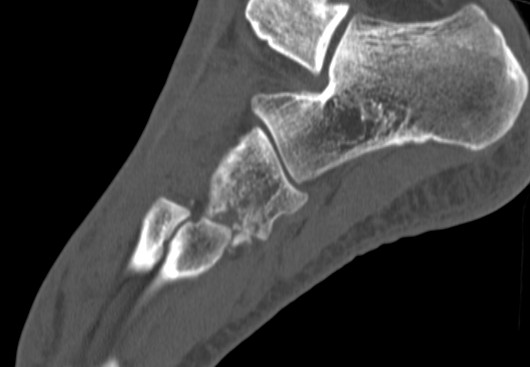

CT scan

Dorsal displacement of metatarsals

Compression fractures / nutcracker of cuboid